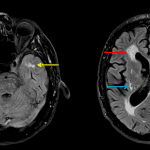

- Multiple remote small vessel ischemic infarcts involving the bilateral cerebellar hemispheres, left hemipons, bilateral basal ganglia and external capsules, and bilateral periventricular white matter

- Markedly age-advanced confluent T2/FLAIR signal hyperintensity in the subcortical and periventricular white matter with notable involvement of the bilateral anterior temporal lobes

- Generalized cerebral volume loss without lobar-specific pattern of atrophy, also advanced for patient age

Cerebral autosomal dominant arteriopathy with subcortical infarcts and leukoencephalopathy (CADASIL)

Multiple remote small vessel ischemic infarcts involving the bilateral cerebellar hemispheres, left hemipons, bilateral basal ganglia and external capsules, and bilateral periventricular white matter on a background of age-advanced confluent T2/FLAIR signal hyperintensity in the subcortical and periventricular white matter with notable involvement of the bilateral anterior temporal lobes as well as generalized cerebral volume loss. For this patient’s age, this appearance is most suggestive of cerebral autosomal dominant arteriopathy with subcortical infarcts and leukoencephalopathy (CADASIL). Recommend genetic testing.